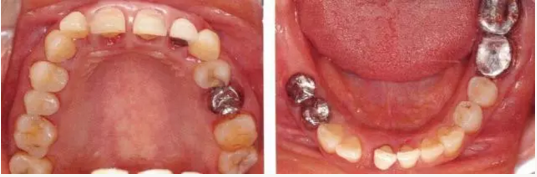

22222222222222.png

▲圖19-2,3

上下頜咬合面照。